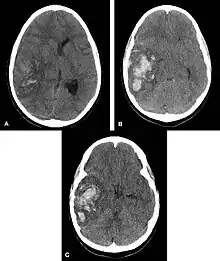

In the elderly population, amyloid angiopathy is associated with cerebral infarcts as well as hemorrhage in superficial locations, rather than deep white matter or basal ganglia. These are usually described as "lobar". These bleedings are not associated with systemic amyloidosis.

Hemorrhagic neoplasms are more complex, heterogeneous bleeds often with associated edema. These hemorrhages are related to tumor necrosis, vascular invasion and neovascularity. Glioblastomas are the most common primary malignancies to hemorrhage while thyroid, renal cell carcinoma, melanoma, and lung cancer are the most common causes of hemorrhage from metastatic disease.

The exact process that leads to bleeding depends on the underlying cause. For intraparenchymal hemorrhage associated with hypertension, small holes in arteries are thought to cause bleeding in the deep penetrating arteries of the brain, which are smaller and thinner than other arteries. These are the arteries that supply blood to the basal ganglia, the thalamus, the brainstem, and deep portions of the cerebellum. Thus, these are the most commonly implicated structures in intraparenchymal hemorrhage associated with hypertension.[2]

Cerebral amyloid angiopathy may cause intraparenchymal hemorrhage even in patients without elevated blood pressure. Unlike hypertension, cerebral amyloid angiopathy does not typically affect blood vessels to deep brain structures. Instead, it is most commonly associated with hemorrhage of small vessels in the cerebral cortex.[2] The strongest risk factor for intraparenchymal hemorrhage associated with cerebral amyloid angiopathy is old age, and cerebral amyloid angiopathy is most frequently seen in patients who already have, or will soon be diagnosed with, dementia.[3]